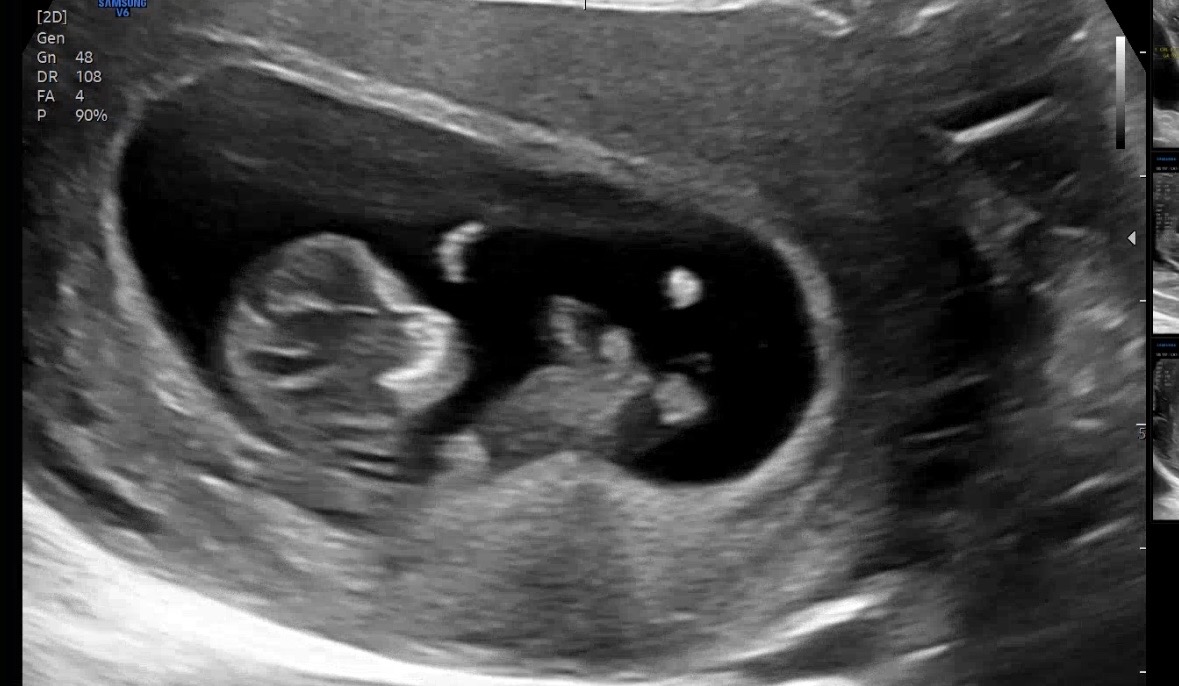

10주 5일차 초음파! 아들일까요??

다리사이에 거대한 무언가가,,,, 아들일까요?